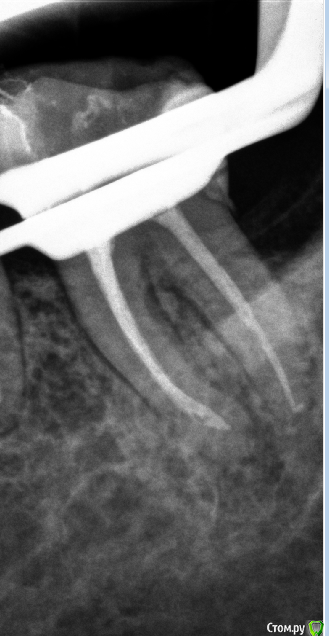

Natalia :) Опубликовано 16 декабря, 2014 Поделиться Опубликовано 16 декабря, 2014 Так. Только стоило отвлечься- понакидали снимков своих. НегодяиСорри,я парочку выложу,потому что мне срочно нужно понять,что я не так делаю...Принимаю самую жесткую критику,потому что и сама все вижу,сравнивая свои с вашими красивыми картинками)работаю первый год,но хочется,конечно, сразу хорошо работать...Про спредеры и гутту поняла,завтра буду выполнять рекомендацию,спасибо)На этом снимке не понимаю,что за хрень нечеткая по стенкам к.к?и тут хрень какая-то пористая,еще и в апикальной трети(здесь полость раскрыта ужасно,знаю,плохой обзор был.Спасибо за внимание 3 Ссылка на комментарий